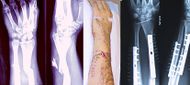

منظر داخلي وخارجي لذراع به كسر مركب. كلا منهما قبل وبعد الجراحة. | |

- - كسر نهاية عظمة العضد " كوليس "